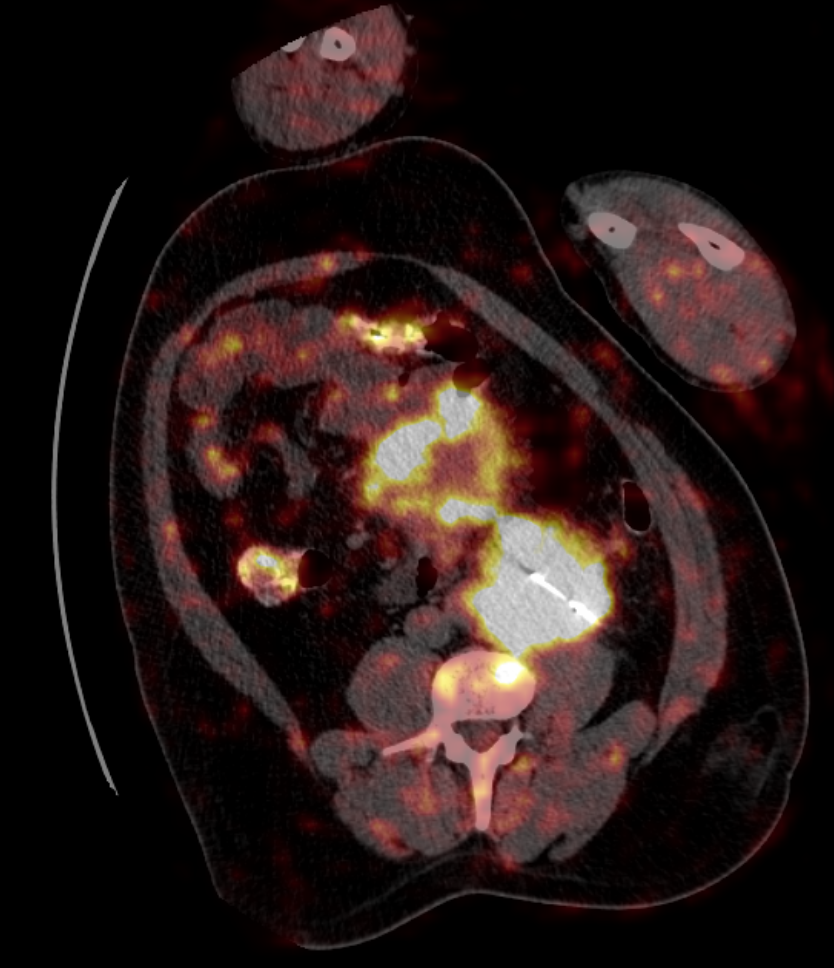

Biopsia guiada por pet-ct